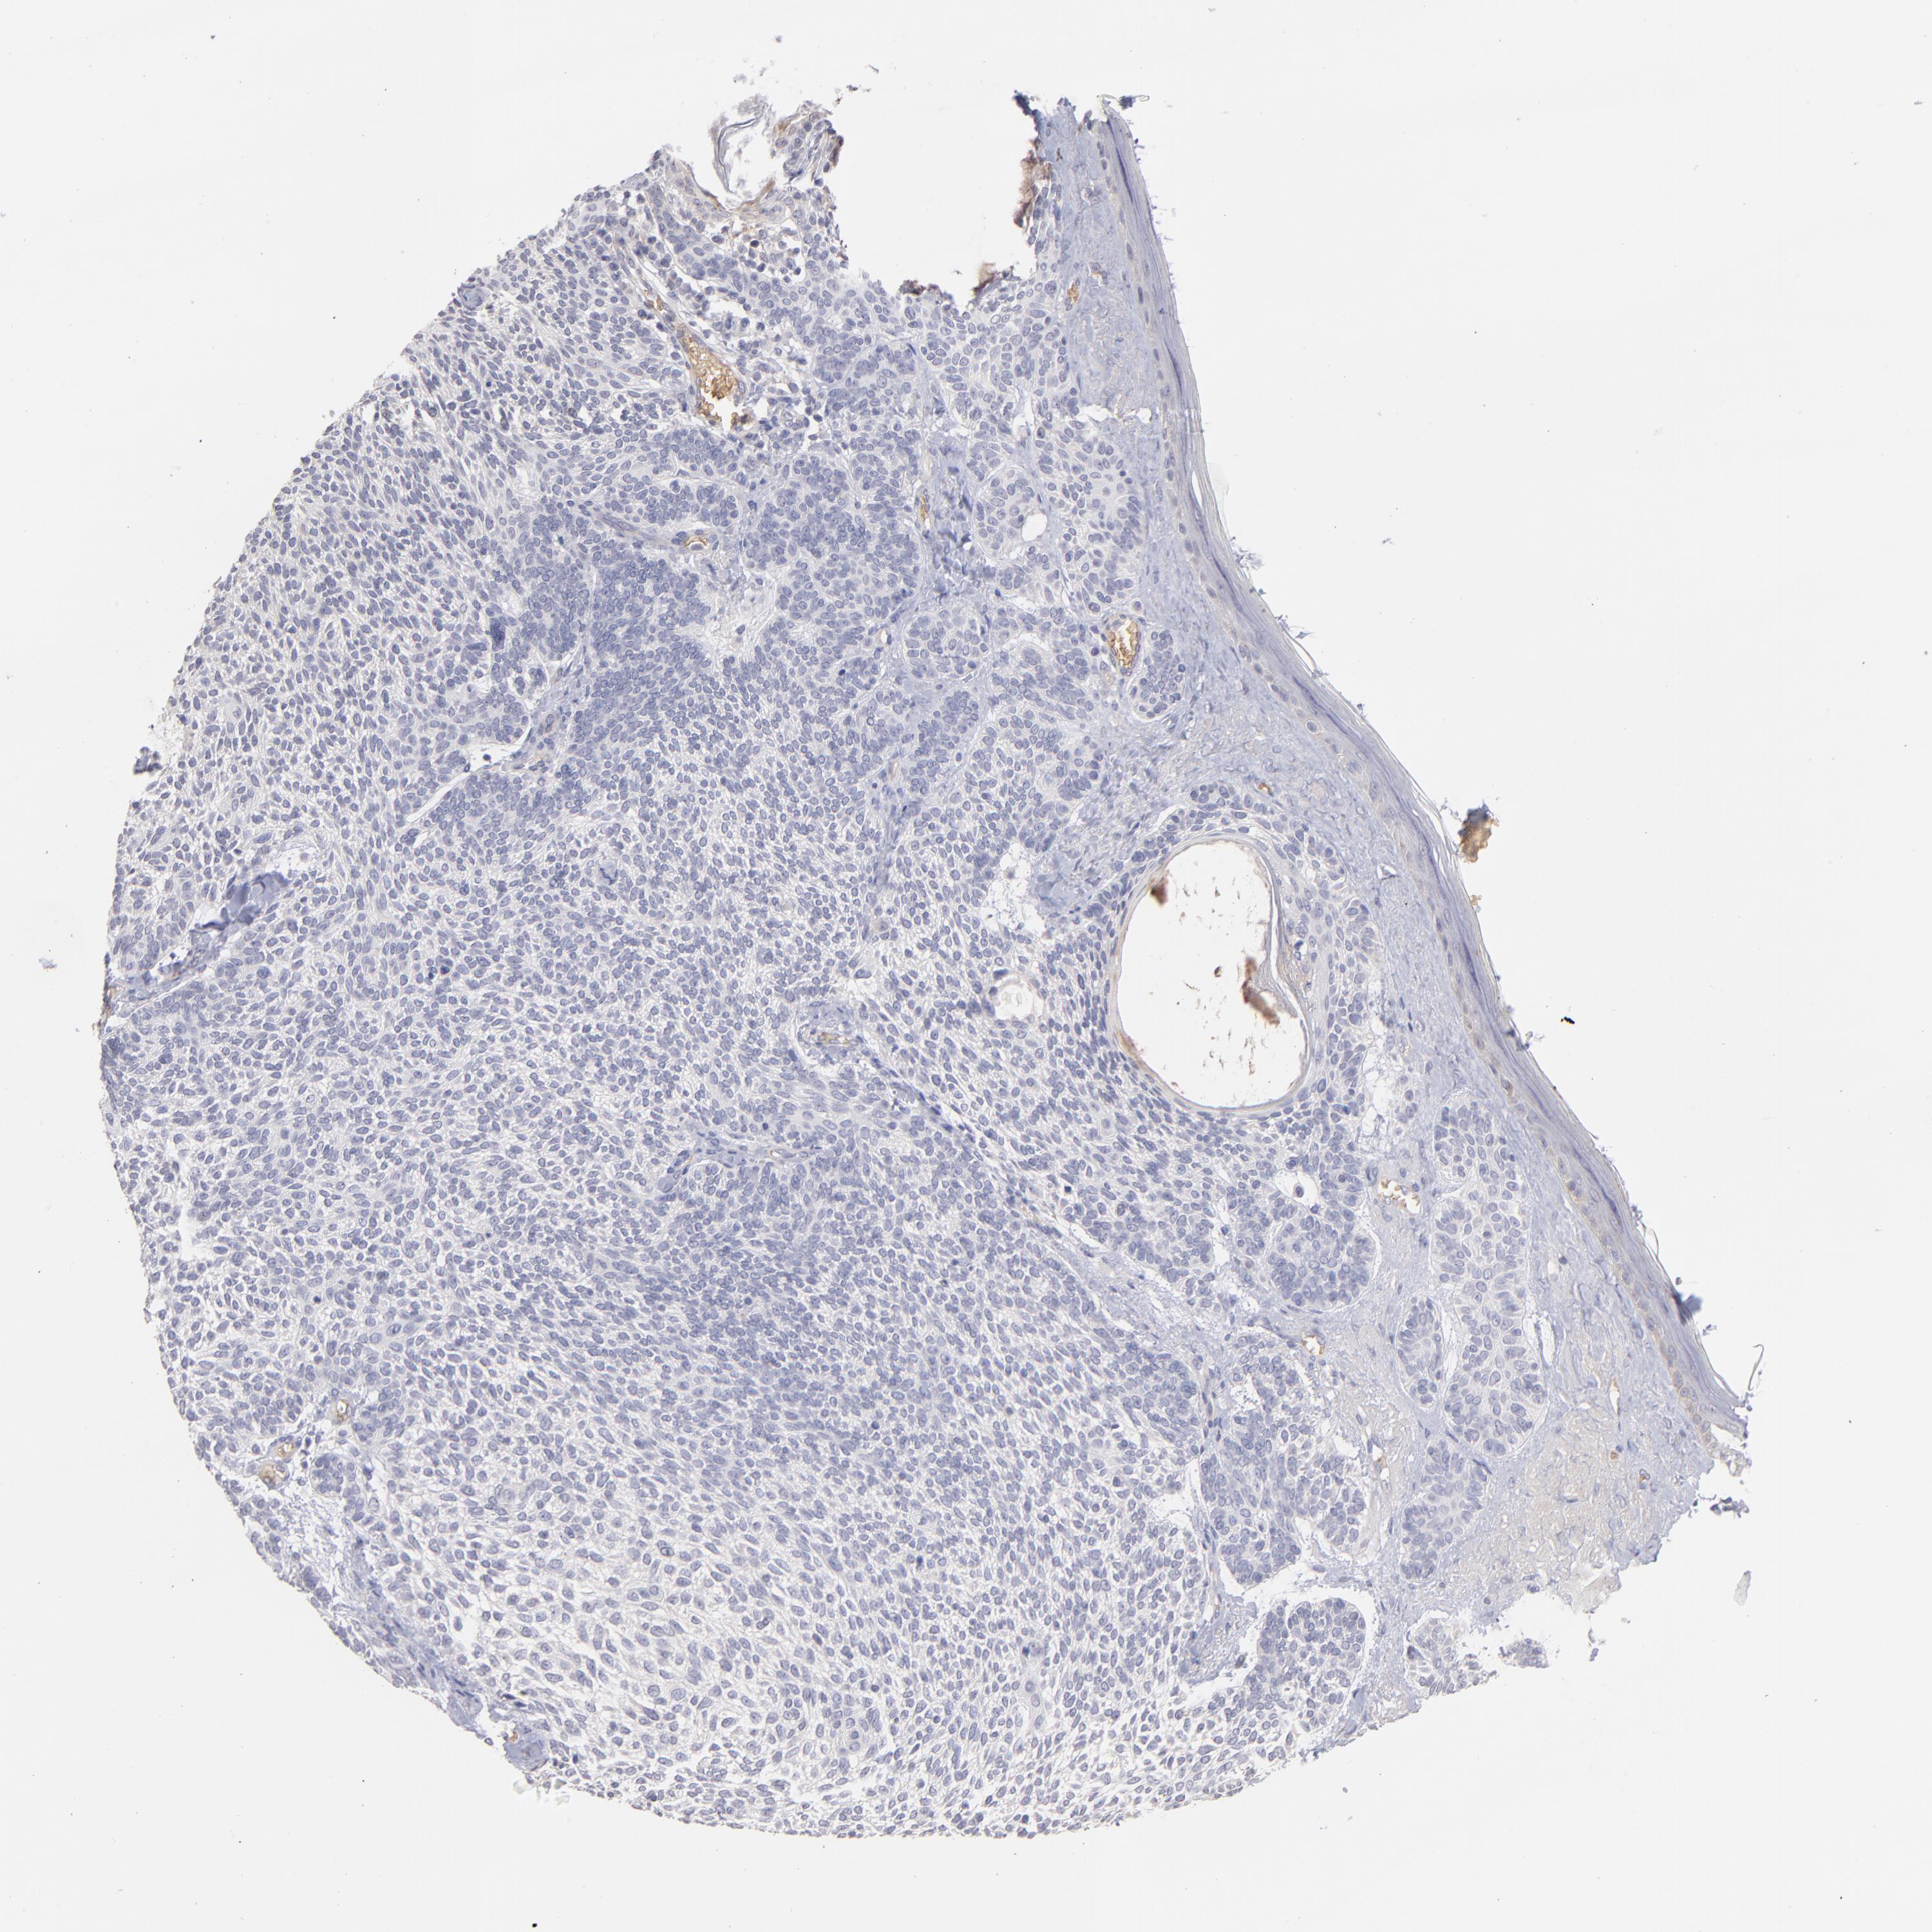

Basal cell and squamous cell cancer

SKIN CANCER - Protein expressioni

A mouse-over function shows sample information and annotation data. Click on an image to view it in a full screen mode. Samples can be filtered based on level of antibody staining by selecting one or several of the following categories: high, medium, low and not detected. The assay and annotation is described here.

Antibody stainingi

Antibody staining in the annotated cell types in the current human tissue is reported as not detected, low, medium, or high, based on conventional immunohistochemistry profiling in selected tissues. This score is based on the combination of the staining intensity and fraction of stained cells.

Each image is clickable and will lead to virtual microscopy that enables deeper exploration of all samples and also displays staining intensity scores, fraction scores and subcellular localization as well as patient and tissue information for each sample.

Antibody HPA052139

Basal cell carcinoma